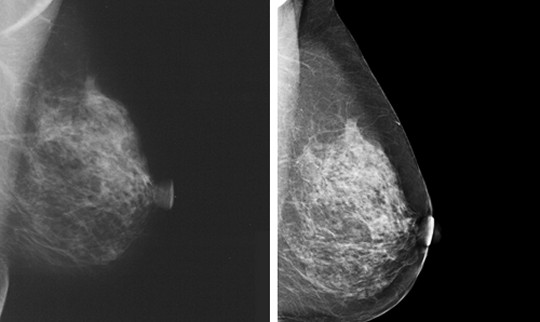

La mamografía es un tipo específico de imagen por RX

que utiliza un sistema Rayos X de baja energía para

explorar las mamas (tejidos blandos).

- Mamografía Convencional: También llamada mamografía analógica, utiliza como soporte de imagen una película radiográfica

- Mamografía digital: También llamada Mamografía Digital de Campo Completo (MDCC), la cual utiliza un sistema de detección de los RX de tipo electrónico y muestra la información obtenida en un monitor de computadora.